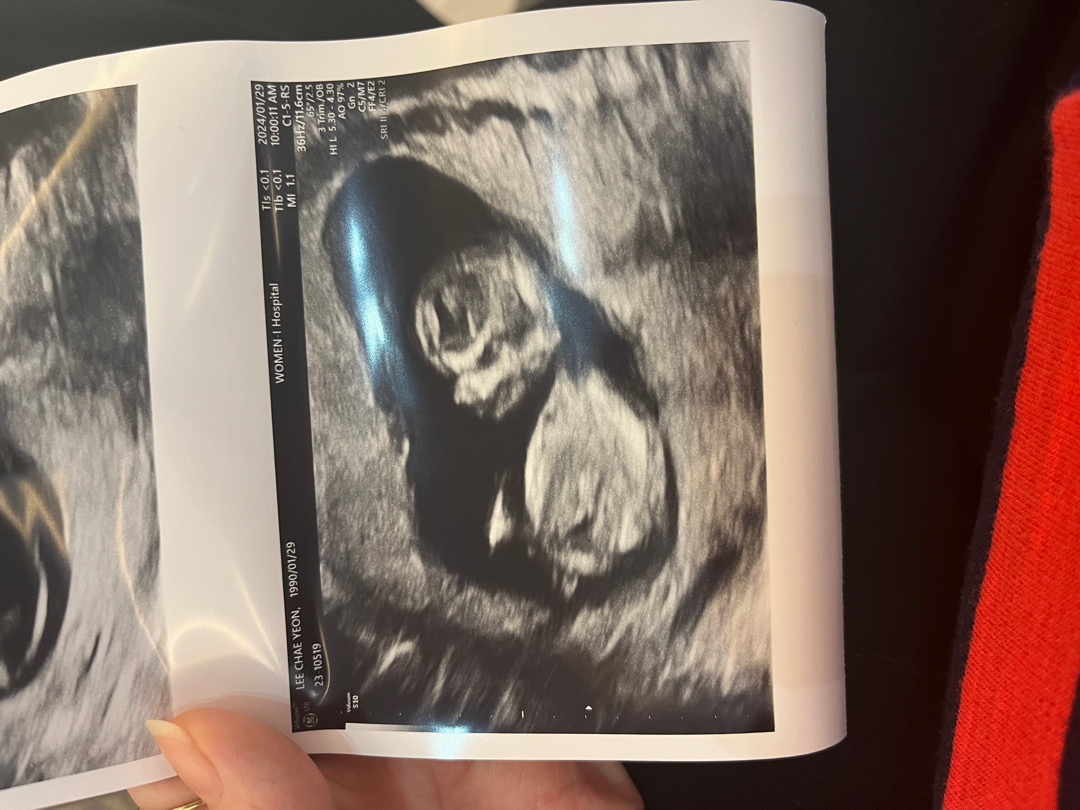

13주 각도법 볼수있을까요?

16주는되야 정확하게알수있대서 궁금해요